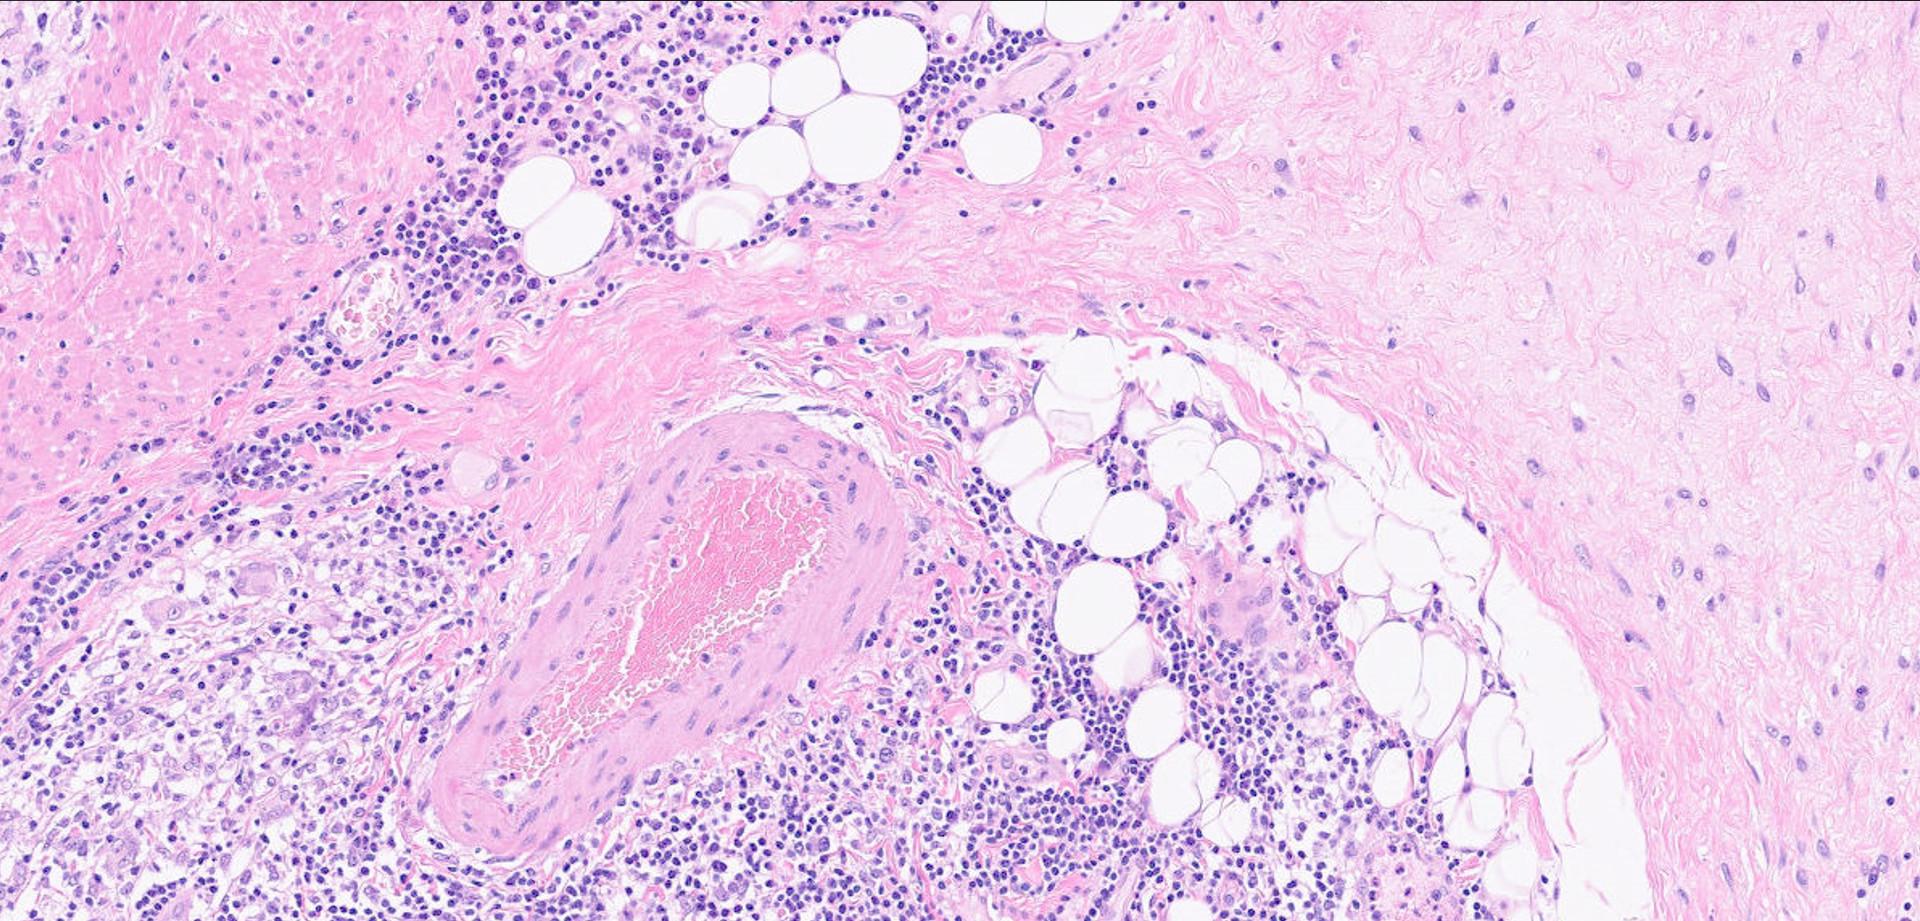

11BIOPSY HANDLING AND OCCUPATIONAL HEALTH: RISK, REGULATIONS AND SOLUTIONS13.11.2053On-demand webinarRead more